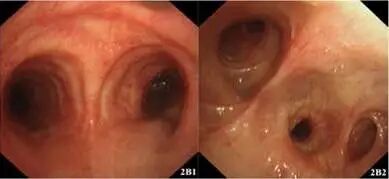

多次BALF真菌培养及支气管粘膜活检回报帚霉菌属,经形态学及基因测序最终鉴定为M. gracilis(图3)。但患者BALF及血GM均为阴性,血培养阴性。结合患者存在活动后呼吸困难、痰量明显增多、气管镜下气道黏膜假膜形成及大量坏死物,病原学多次提示M. gracilis,根据2011年国际心肺移植协会(ISHLT)共识[1]考虑诊断为“侵袭性支气管-肺帚霉感染(确诊)”。

图3. M. gracilis光镜下形态(3A. 400倍放大,3B. 1000倍放大)